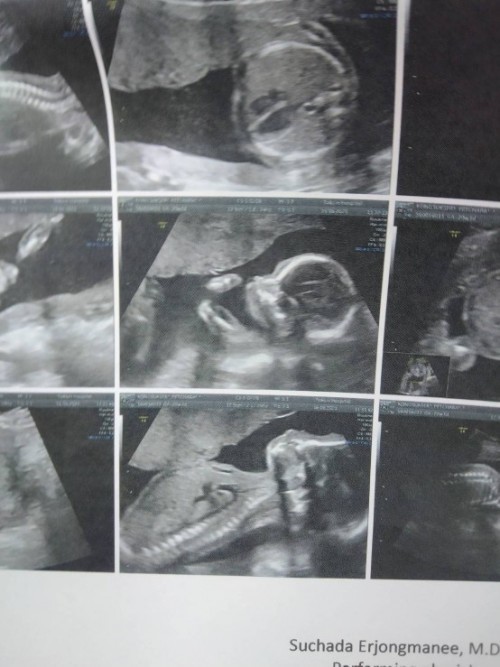

24week6d อยากเจอแล้วตื่นเต้น🥰